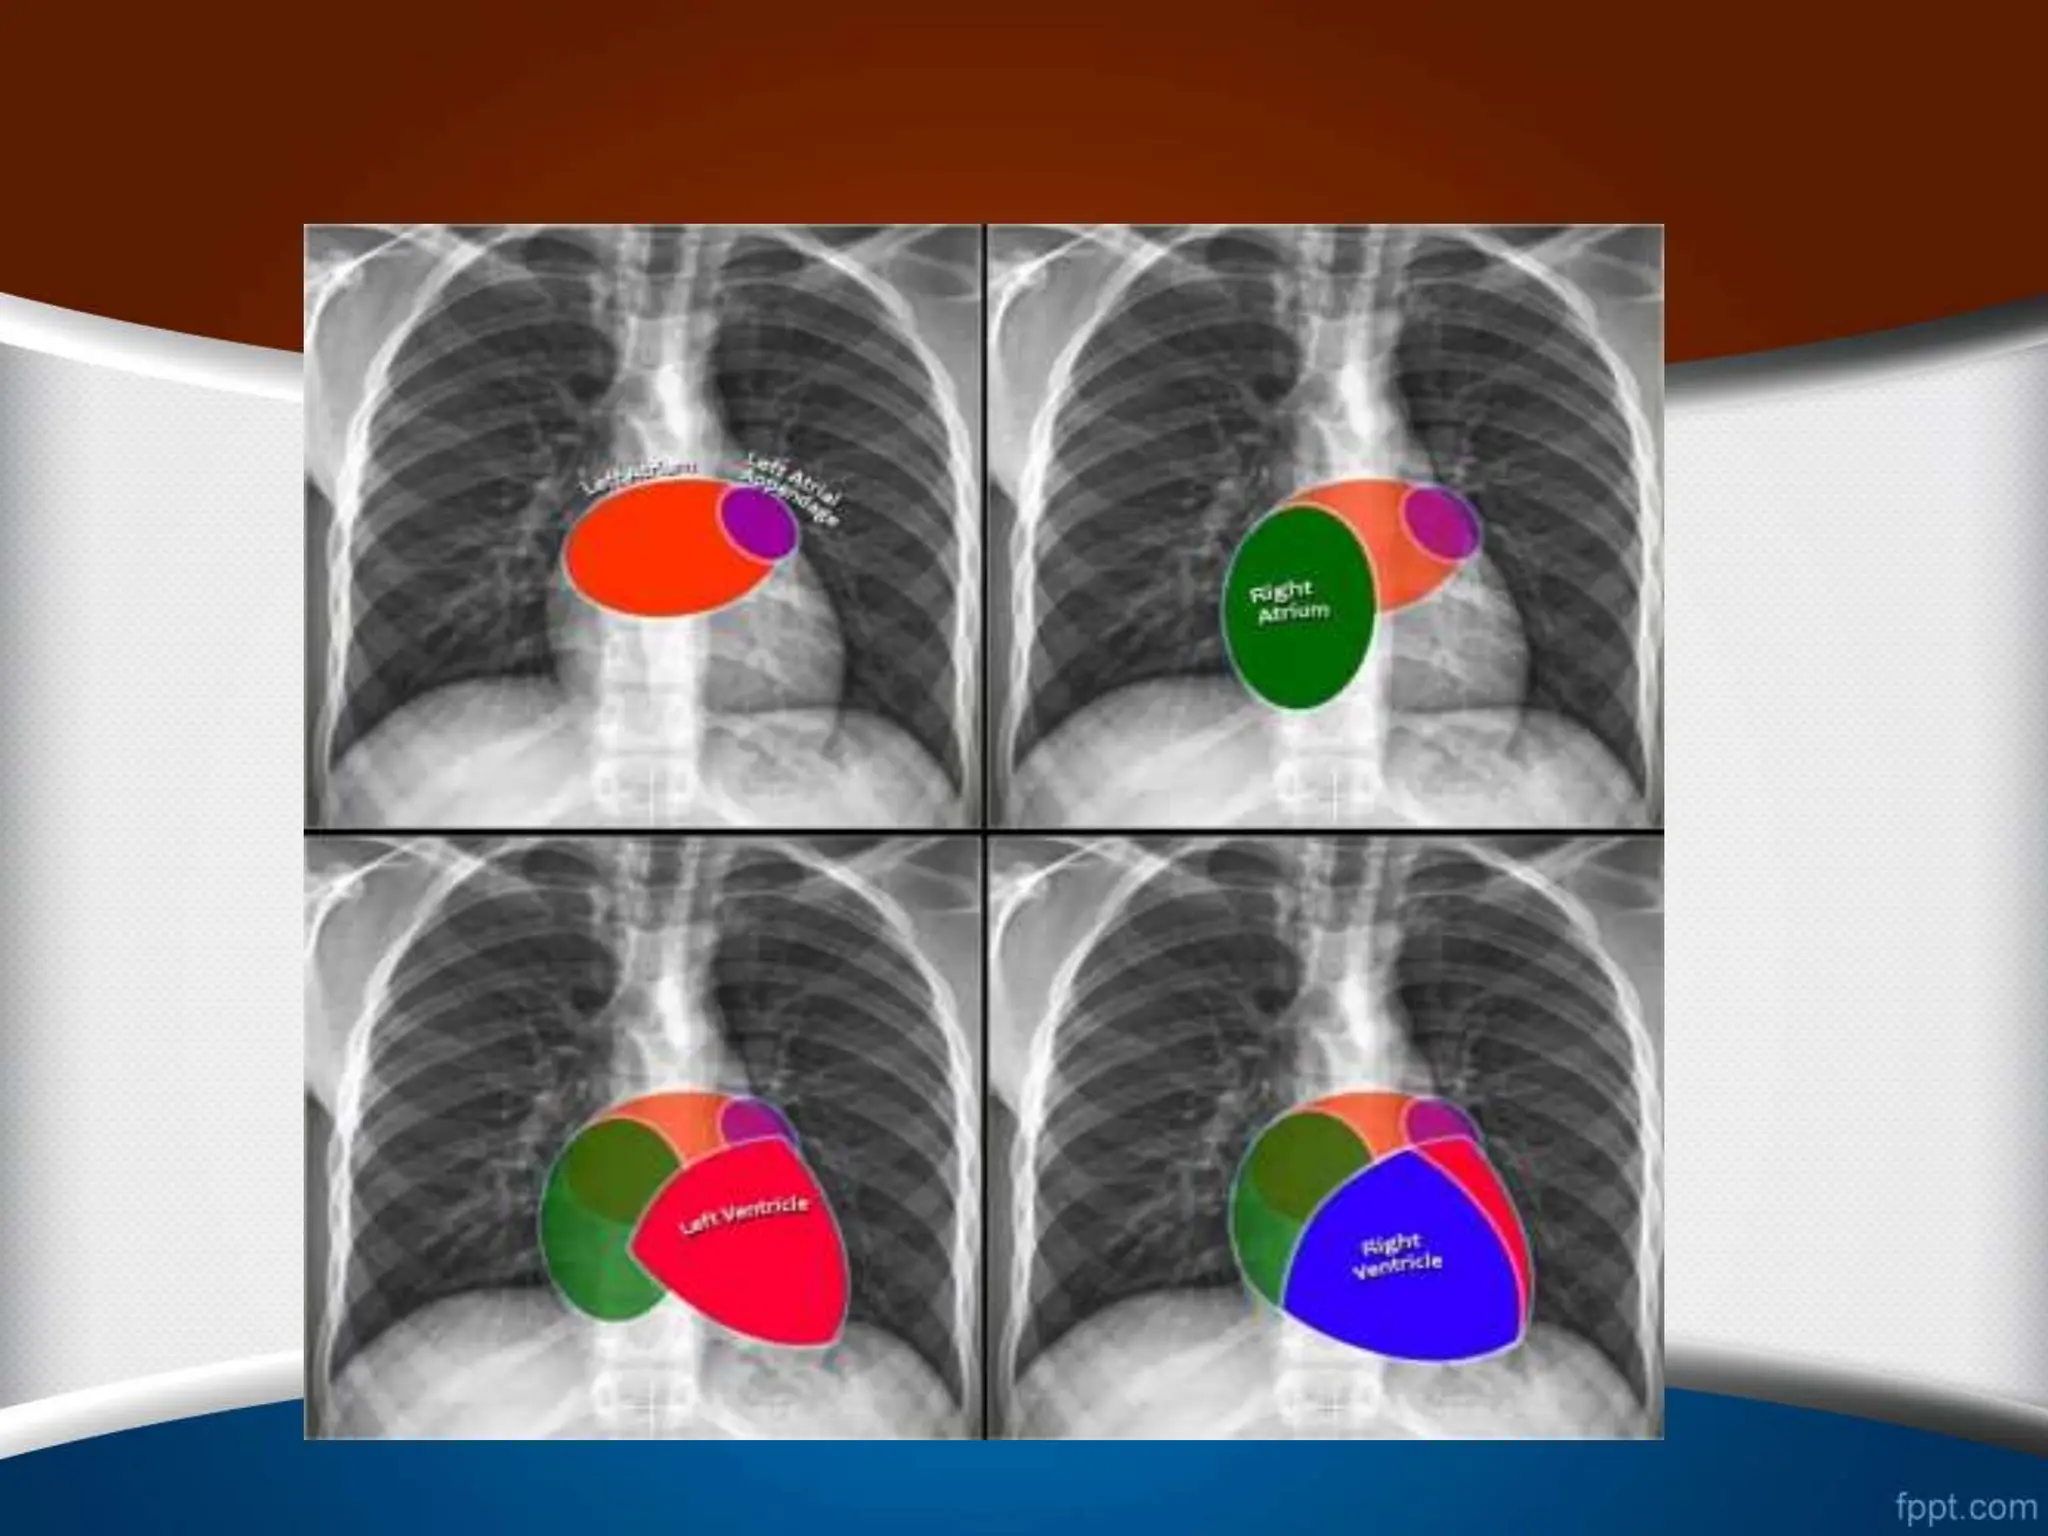

‫قلب‬ ‫های‬ ‫حاشیه‬

‫چپ‬ ‫بطن‬ ‫بزرگی‬

‫راست‬ ‫بطن‬ ‫بزرگی‬

‫گرافی‬ ‫در‬ ‫هم‬ ‫مورد‬ ‫این‬ ‫در‬

PA

‫نوک‬ ‫شدن‬ ‫گرد‬ ‫سینه‬ ‫قفسه‬

‫دی‬ ‫دیافراگم‬ ‫باالی‬ ‫طرف‬ ‫به‬ ‫آن‬ ‫جایی‬ ‫جابه‬ ‫با‬ ‫همراه‬ ‫قلب‬

‫ده‬

‫شود‬ ‫می‬

‫چپ‬ ‫دهلیز‬ ‫بزرگی‬

‫راست‬ ‫دهلیز‬ ‫بزرگی‬